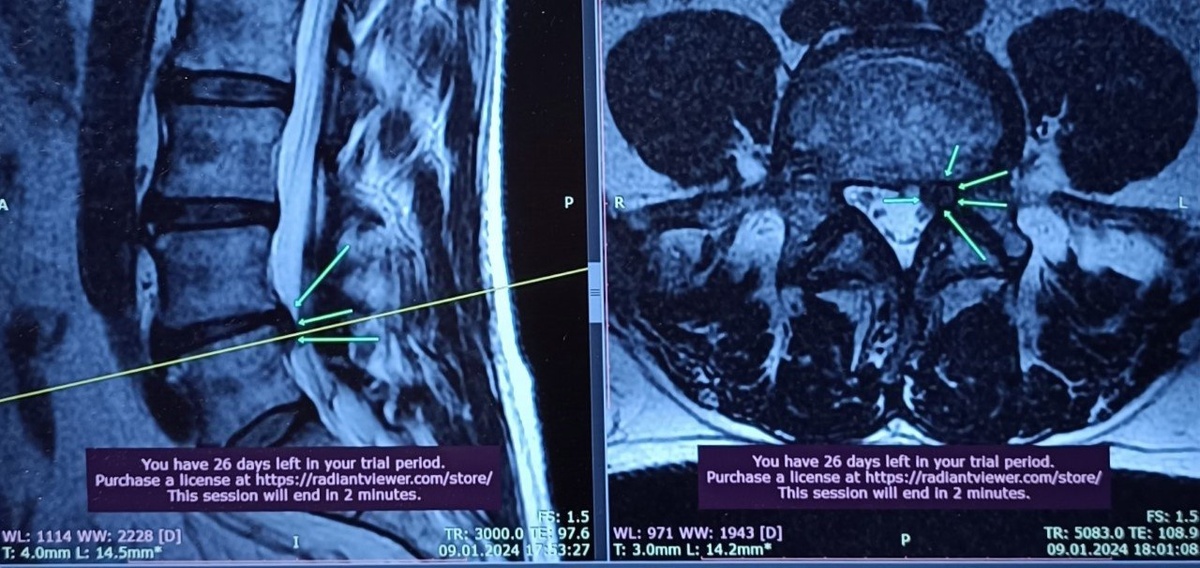

К концу первого месяца сила в ноге восстановилась полностью, боль практически исчезла. Через четыре месяца контрольное МРТ показало уменьшение грыжи.

«Знаете, что я почувствовал на контрольном МРТ? Я не верил своим глазам, что грыжа уменьшилась БЕЗ операции!» — признается Сергей, и в его голосе до сих пор звучит изумление.

Выше на фото вы можете увидеть динамику МРТ Сергея - до лечения ( январь 2024г) - через 4 месяца после ( май 2024 г). Стрелками обозначено место грыжи